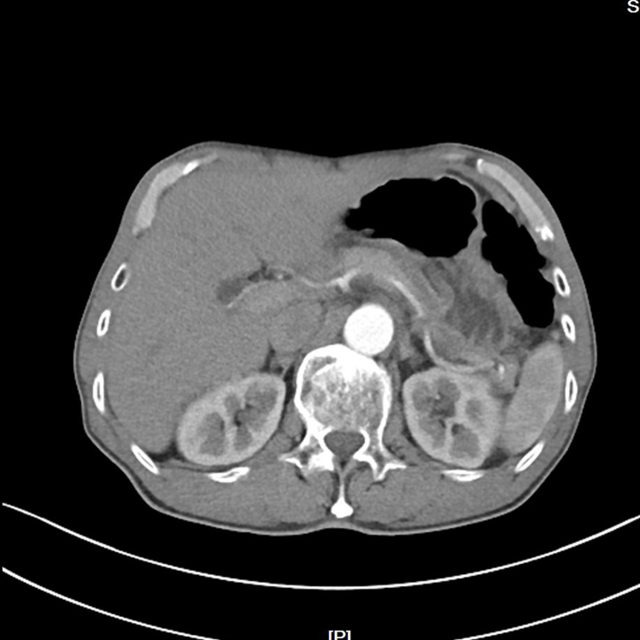

▲新辅助治疗前